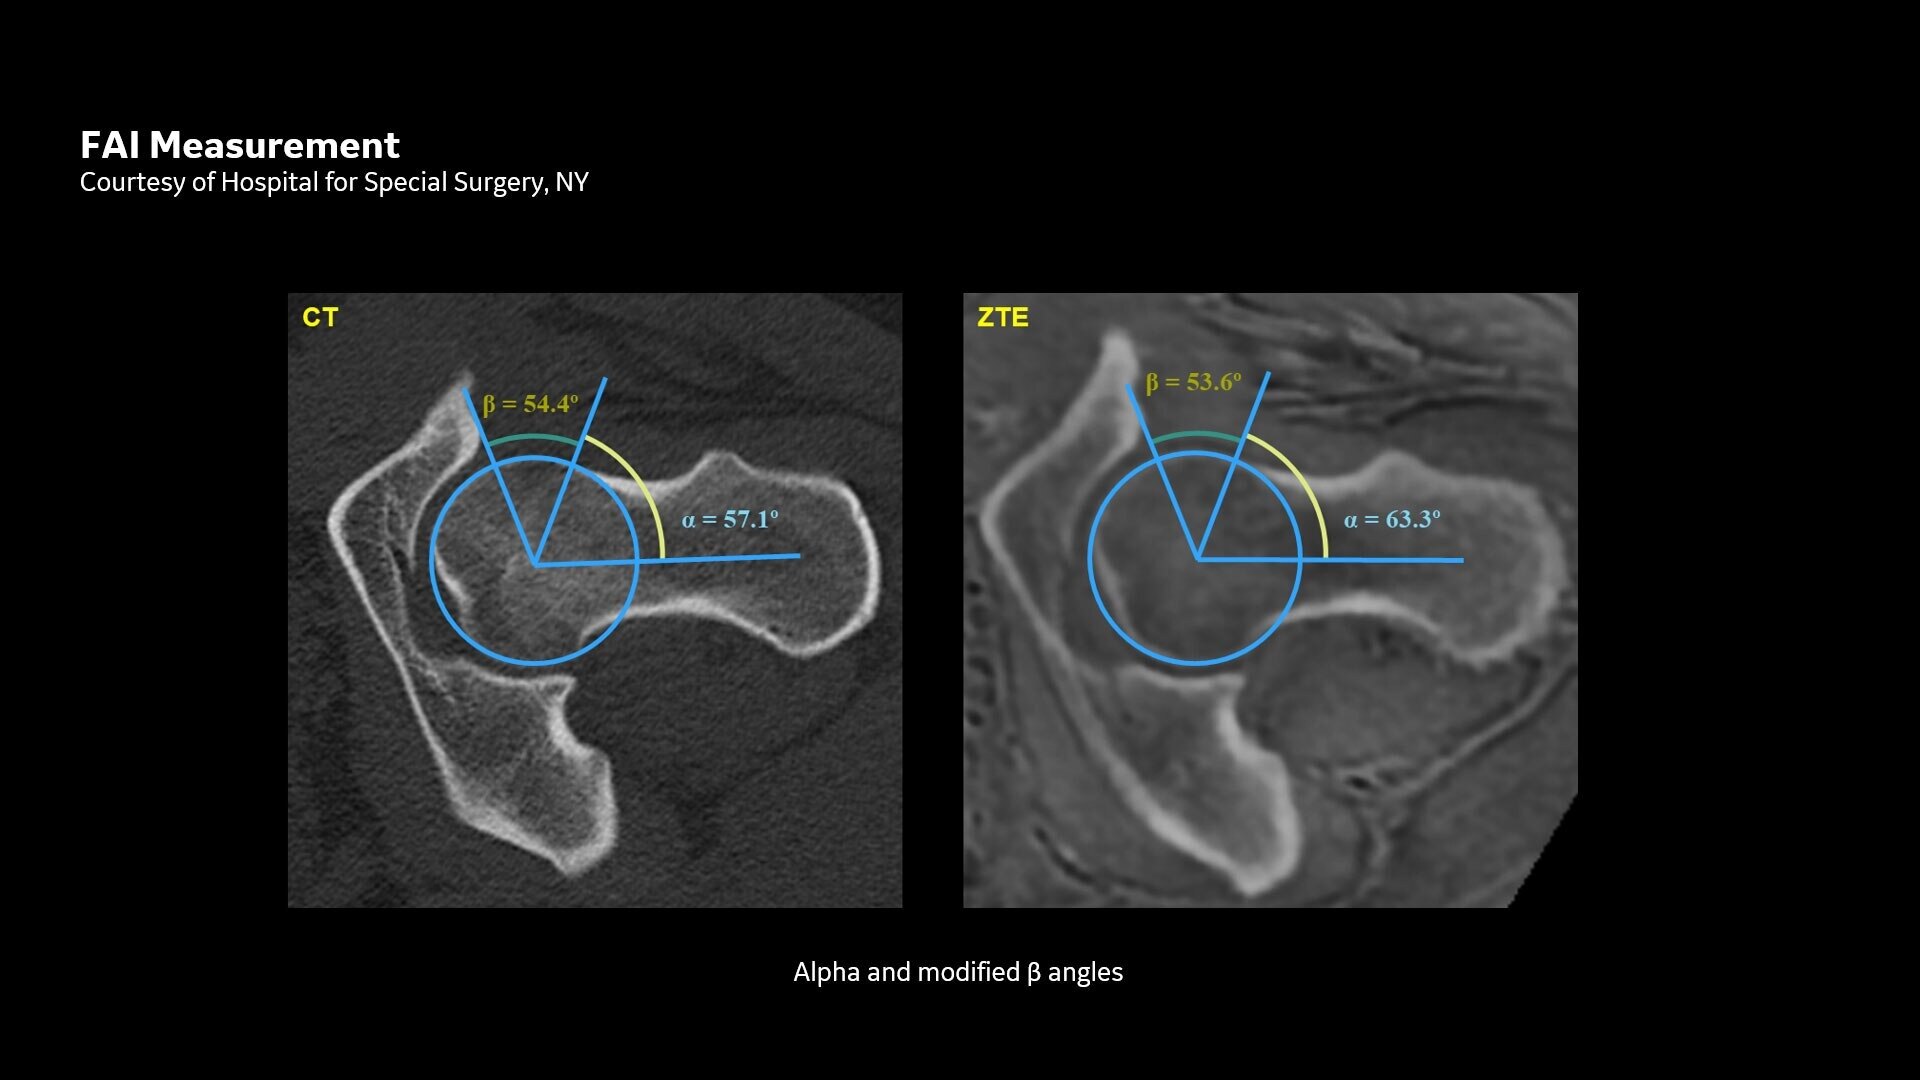

Available for all anatomies without ionizing radiation, oZTEo delivers images of bone morphology, calcification, ossification and fractures. oZTEo complements conventional MR soft tissue exams with perfect co-registration and provides 3D isotropic imaging using a radial ZTE acquisition, with inherent motion insensitivity. Use oZTEo with Volume Illumination for realistic 3D rendering.

MR bone imaging provides a CT-like image contrast without ionizing radiation, making it an attractive alternative for pediatric and pregnant patients where ionizing radiation is a concern. In addition, it provides a welcome alternative when longitudinal CTs are required, particularly when low-dose CT systems are unavailable.